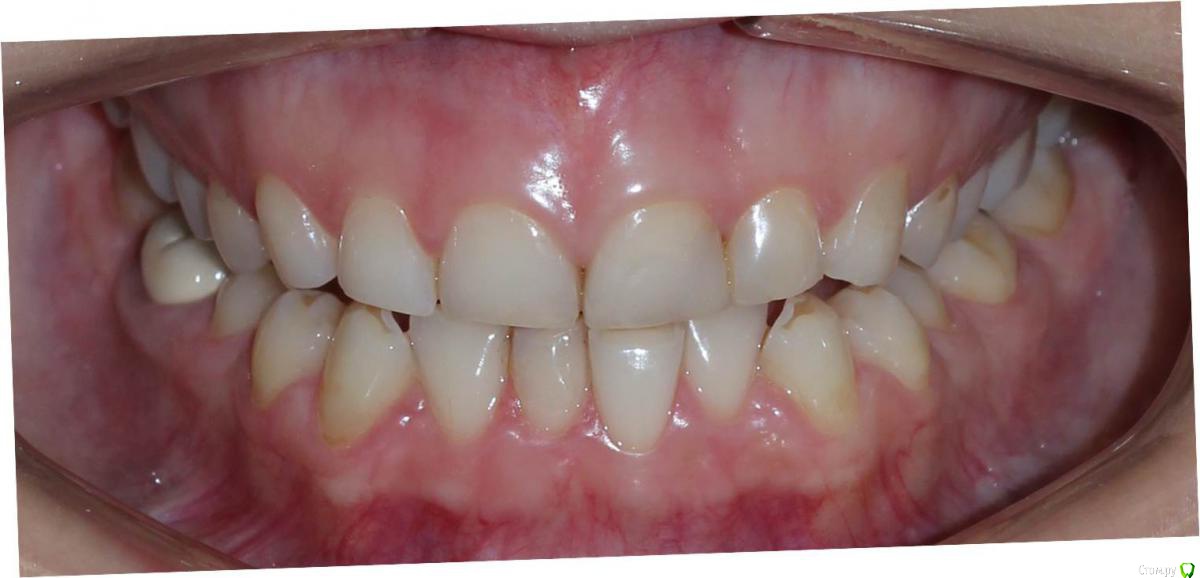

Сева северный Опубликовано 9 декабря, 2015 Поделиться Опубликовано 9 декабря, 2015 Ко мне обратилась молодая девушка, не довольная своей улыбкой. Был проведен этап планирования.... анализ улыбки ..(DSD), (wax up) и примерка (mock up)Проведенный этап...с мотивировал пациентку . 15 Ссылка на комментарий

Сева северный Опубликовано 11 декабря, 2015 Автор Поделиться Опубликовано 11 декабря, 2015 (изменено) Как вы определяете когда надо делать хир.удлинение коронки, а когда просто удлинить без хирургии. По стертым режущим краям,похоже что не было нарушения прорезывания...зондировали до ЦЭС? Или по десневой улыбке скромной решили пойти апикально?Я сделал только планирование.... Ход мысли был следующий: Длина центральных резцов 19-20 мм. Длина коронковой части зуба центрального резца 7-8 мм. Оптимальная длина 10.5. По результату пациентка с мотивирована на ортодонтию , с коррекцией gammy smile. Решение по хирургии, примем по результатам ортодонтии. Изменено 11 декабря, 2015 пользователем Сева северный 1 Ссылка на комментарий